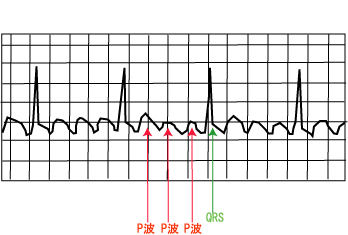

心房細動の心電図は、絶対不整脈と呼ばれます。

心房は毎分300〜600程度の震えを生じていますが、心筋には不応期があるので、 心房→心室への興奮の伝導が常に起こるわけではなく、 あるとき、たまたま心室へ興奮が伝わるため一定の間隔とはならずRR間隔はばらばらになります。

心房細動